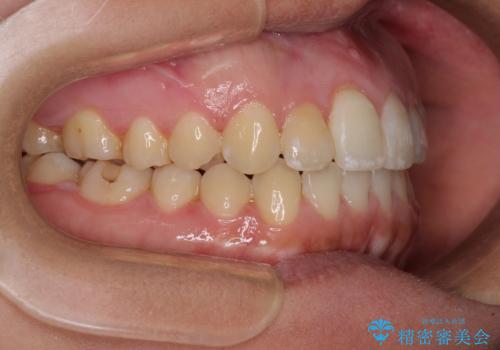

治療開始後すぐに妊娠され、つわりと闘いながらの矯正治療となりました。

上下顎でゴムかけを行ったのですが、早く終わらすためにしっかりと装着していただき、無事出産前に装置を外すことができました。